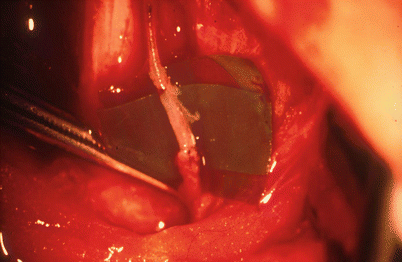

To facilitate the suturing and handling the lymphatic vessels, a green plastic sheet is put underneath the vessels. Addition of some drops of Ringer’s solution mixed with heparin helps to discriminate the front and back vessel walls by suspending the vessels.

3.3.2 End-to-End Anastomosis

The first stitch is the most difficult one since the wall is collapsed. It might be helpful to add a small amount of Ringer’s solution mixed with heparin helping to lift the wall (Fig. 3.3). In very small lymphatic vessels with fibrosis around the lumen, it might be advisable to only fix the outer layer with the stitches. The content of the lumen of the vessel can then drain into the graft.

End-to-end anastomosis, first corner stitch. Graft with translucent wall above, sclerosed lymphatic vessel of lymphedematous tissue with the lumen surrounded by fibrosed wall below (© Baumeister)

Leakage will not be a problem since the pressure is low (Fig. 3.4).

End-to-end anastomosis completed. Graft filled with lymph (© Baumeister)

The graft is filled with lymph at the end of the anastomosis also when the wall of the lymphatic vessel within the edematous tissue shows fibrosis (Fig. 3.5).

End-to-end anastomosis with three stitches (© Baumeister)